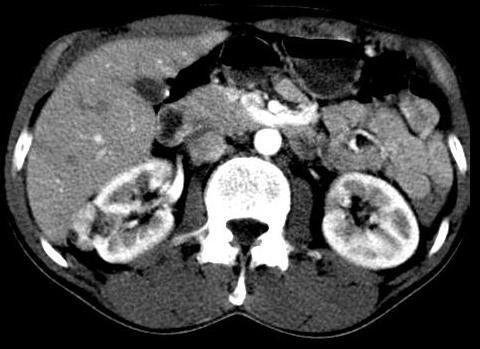

КТ без контраста: примеры изображений и рекомендации